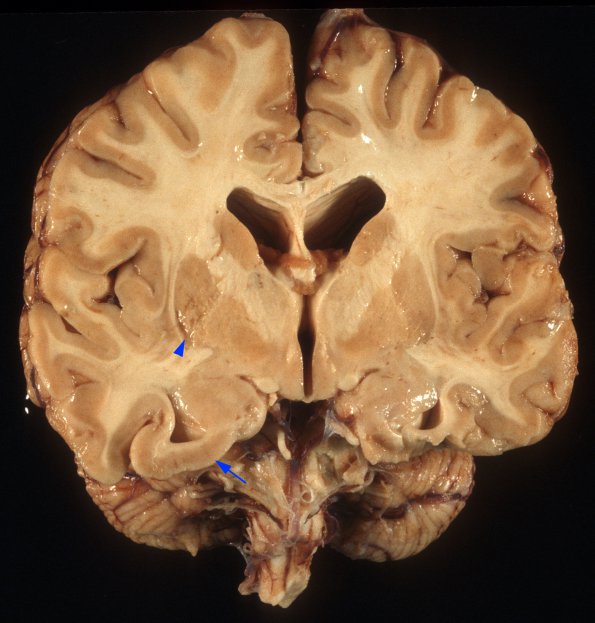

This larger image shows granularity in the basal ganglia (arrowhead) and an area of focal possible polymicrogyria (arrow)